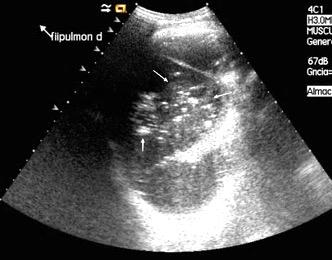

Patrón ecográfico de empiema

Anecoico.....0%. (0 de 47)

Complejo no septado no hiperecoico... ……………..0% (0 de 36)

Complejo, no septado hiperecoico......100% (2/2)

Complejo septado …35% (11 de 31)

Ecogénico homogéneo .... 100% (2 de 2)

Wang T et al. Value of ultrasonography in determining the nature of pleural effusion. Analysis of 582 cases. Medicine 2022.

Chih-Yen Tu et al. Chest Ultrasound Study Pleural Effusions in Febrile Medical ICU. Chest 2004